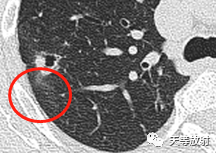

囊腔壁厚薄不一。

囊腔周围见长条索状影,代表组织受到牵拉聚拢。此时病例的影像学特点:

病变发生于右肺上叶;

实性结节+囊腔

实性略呈分叶状,周围见长条索状影;局部收缩,胸膜凹陷;

囊腔壁厚薄不一。这个结节表现出一定的恶性征象:分叶状实性结节,胸膜凹陷及血管聚拢改变。